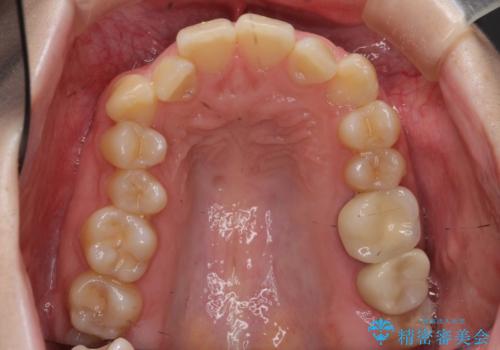

- 前歯の並びと下の歯のがたつきを主訴に来院。

左下にがたつきが集中していました。

歯を抜かずに、左上および左下の奥歯を後ろに送ることで隙間を確保しました。

左下の第一小臼歯が歯列からはみ出て、近心傾斜しており、抜歯の上ワイヤー矯正の選択肢もお話ししましたが、非抜歯で、インビザライン矯正を希望されました。左下の第一小臼歯は完全に並べることは難しいと初めから説明し、納得いただいた上で治療開始しました。

結果それなりに並んで問題ない状況にはなったと思います。